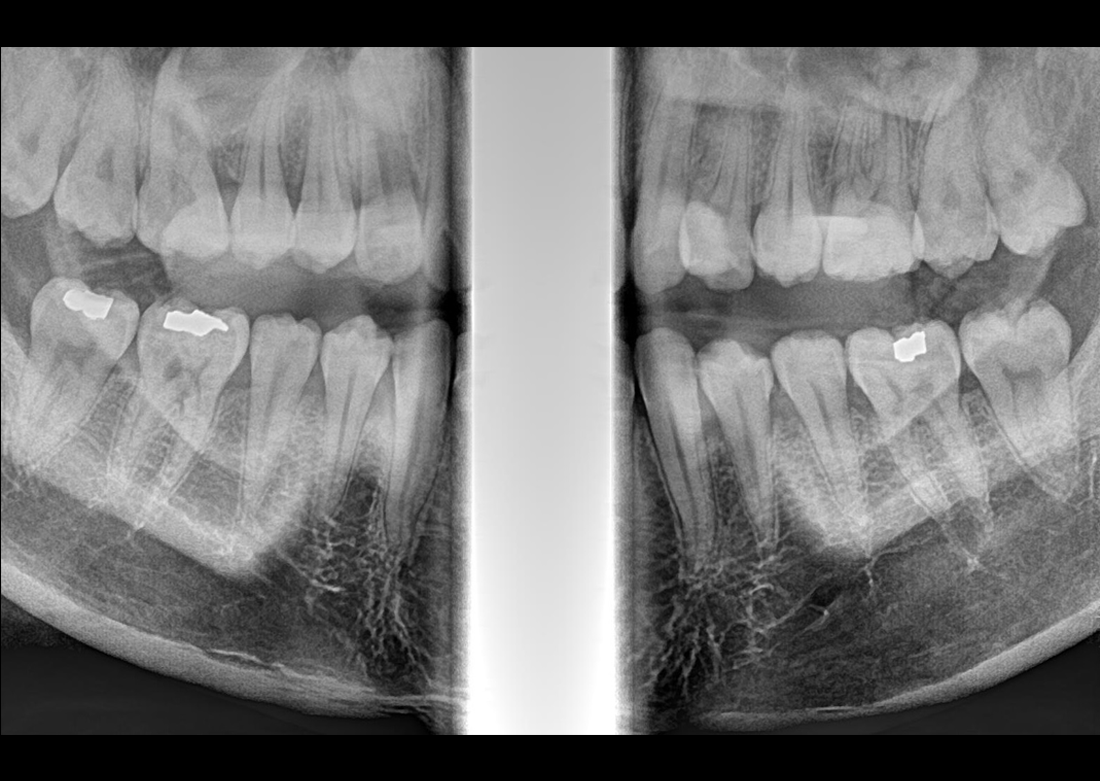

Panoramic

MÜKEMMEL GÖRÜNTÜ KALİTESİ

KLİNİK FOTOĞRAFLAR

Yılların tecrübesi ve geliştirdiği know-how teknolojileri ile muhteşem teşhis görüntüleri yaratmak Genoray firmasının herzaman gururu olmuştur..